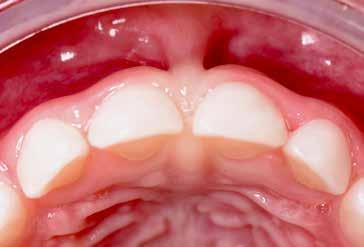

Figg. 9-11 > Intervento di frenulectomia con laser a diodo.

Figg. 12, 13 > Controllo dopo ventiquattro ore.